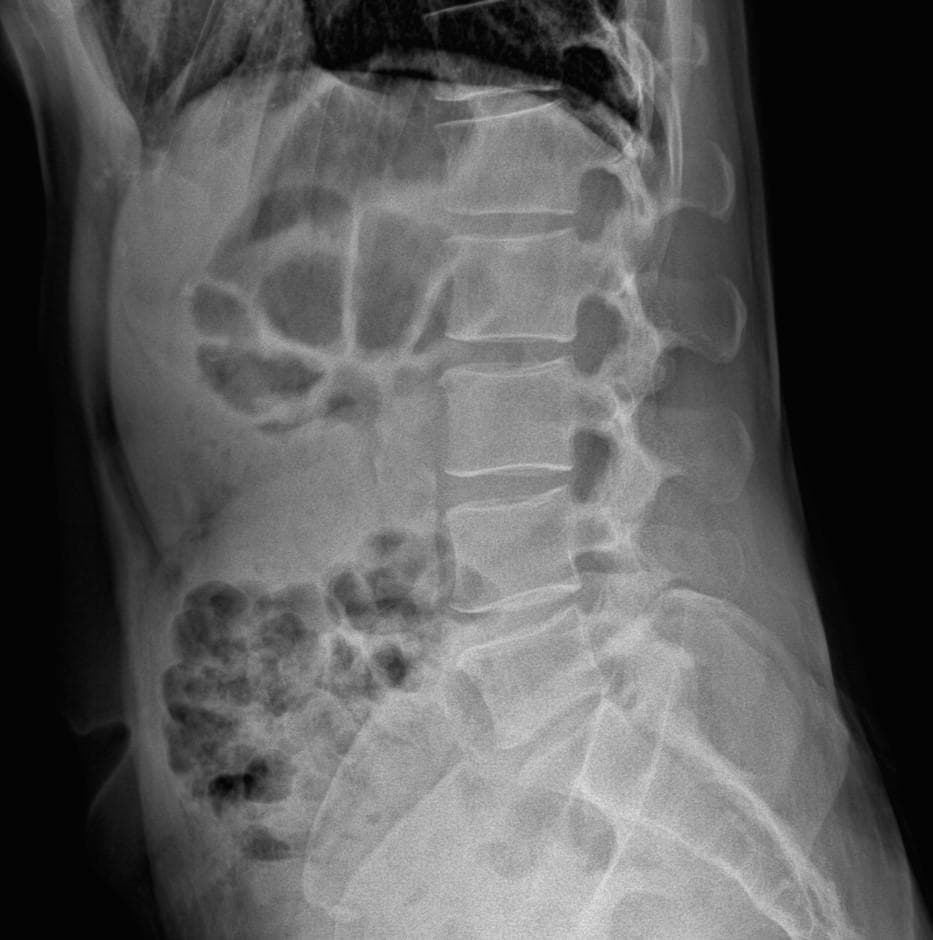

엑스레이 상에서는 요추 배열이 전반적으로 잘 유지돼 보입니다. 마나 일부 요추 간격이 좁아진 부위가 있어 보입니다. 말씀하신 것처럼 특정 동작에서 찌릿 혹은 뜨끔하거나, 최근 뻐근함이 생기는 건 디스크 초기나 근육, 인대 긴장에서도 나타날 수 있습니다.

허리의 커브가 줄어들어있다는것을 제외하고는 크게 문제가될만한 부분은없는데요 통증과불편감이 지속된다면 MRI와같은 정밀검사가 필요할수있습니다

사진상 요추 사이의 간격이 다소 좁아 보이며 간격이 좁다는 것은 퇴행성 변화를 의미하며 척추의 정렬 또한 큰 전위는 없어 보이나 허리 곡선이 정상보다는 조금 감소한 상태로 이러한 경우 근육의 긴장이나 만성적인 통증이 발생할 수 있습니다.

엑스레이 검사를 통해서는 현실적으로 뼈 위주의 평가만 가능하며 정밀하고 자세하게 평가를 내리는 것은 어렵습니다. 올리신 엑스레이 사진들에는 특별히 문제가 있다고 볼만한 소견이 크게 있어보이거나 하지는 않습니다.

우선 현재로썬 척추와 척추 사이인 디스크 공간이 좁지는 않아보이지만 다소 요추의 커브가 감소되어 있어 보입니다.